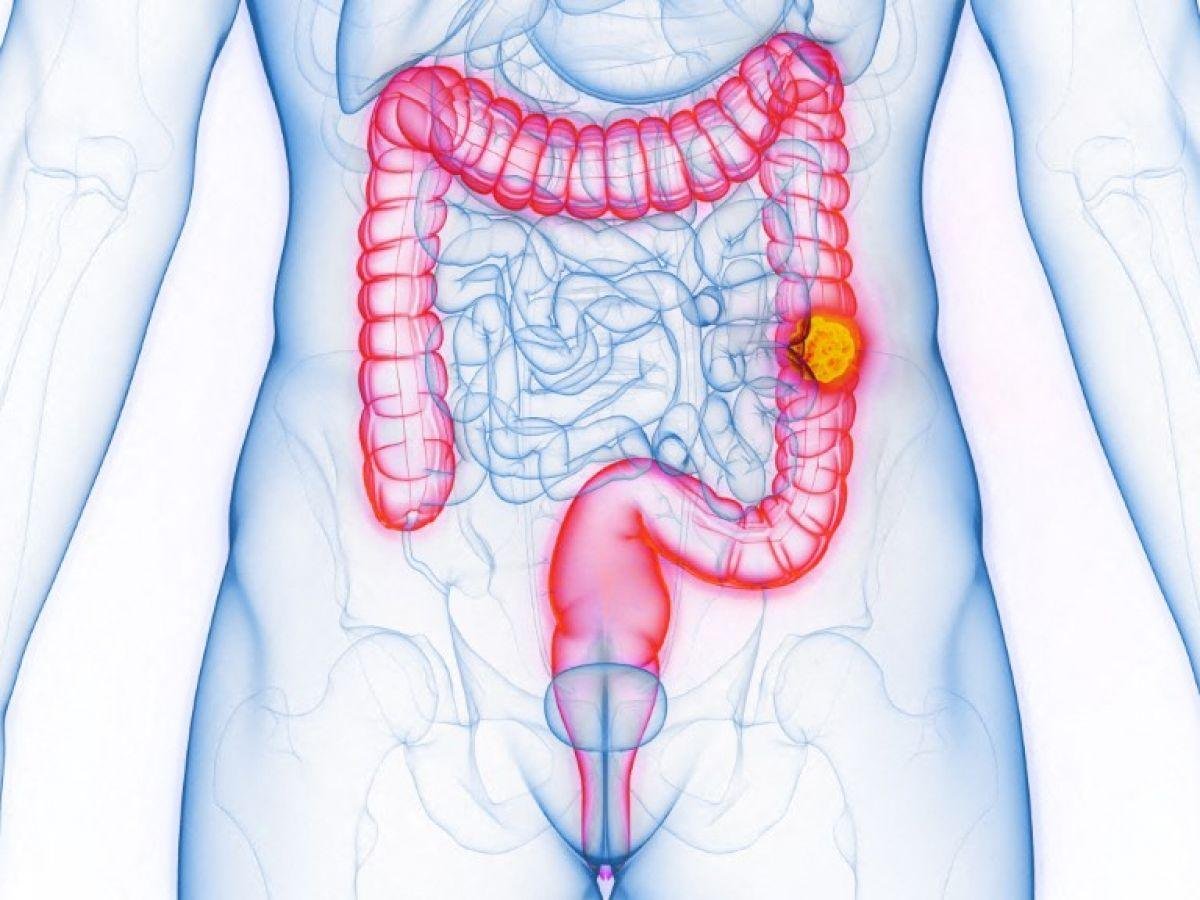

En France comme dans de nombreux pays à travers le monde, l’incidence du cancer colorectal chez les jeunes est à la hausse, sans qu’aucune explication n’ait pu être trouvée pour le moment. Pour la première fois, une piste a été identifiée. Celle d’une toxine, la colibactine, présente dans notre intestin.[Lire l'article en intégralité]